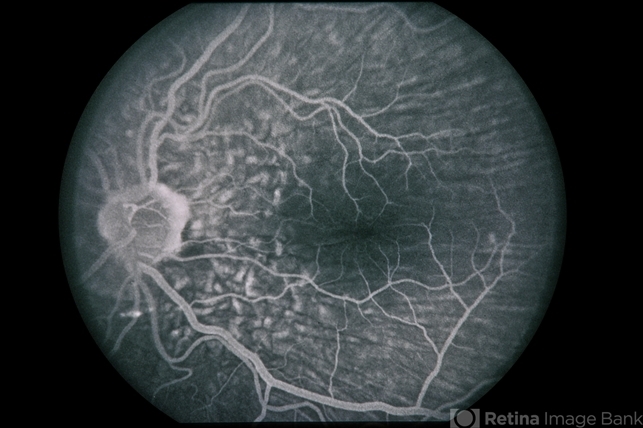

Hypotony from OverFiltration

45-year-old Hispanic male with hypotony from over-filtration.